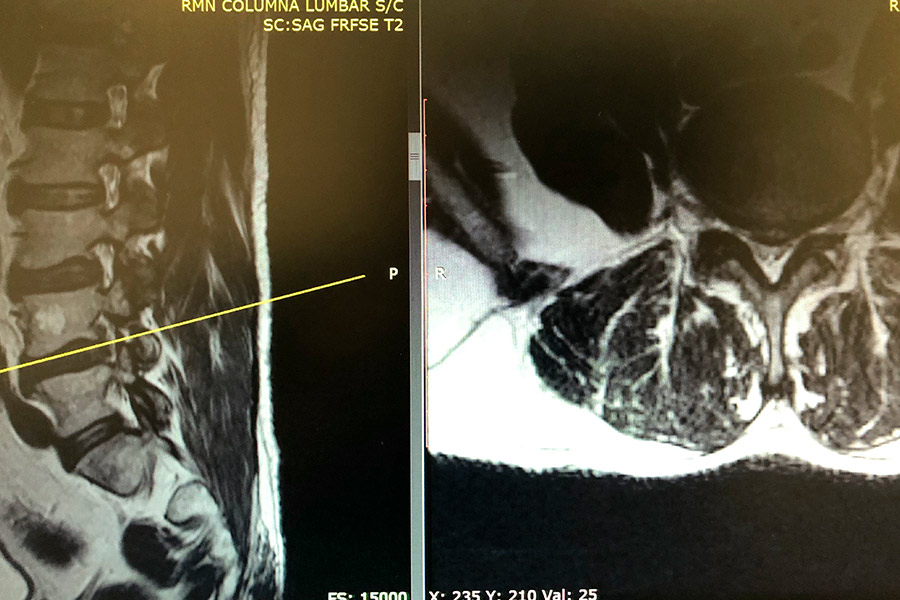

Caso clínico: endoscopia de columna multinivel L4L5 y L5S1

Los síntomas que presentaba el paciente eran dolores acentuados en las piernas, claudicación a la marcha y calambres y hormigueos en las piernas.

Durante la intervención quirúrgica, se abordarán los dos niveles mediante la técnica de endoscopia de columna.